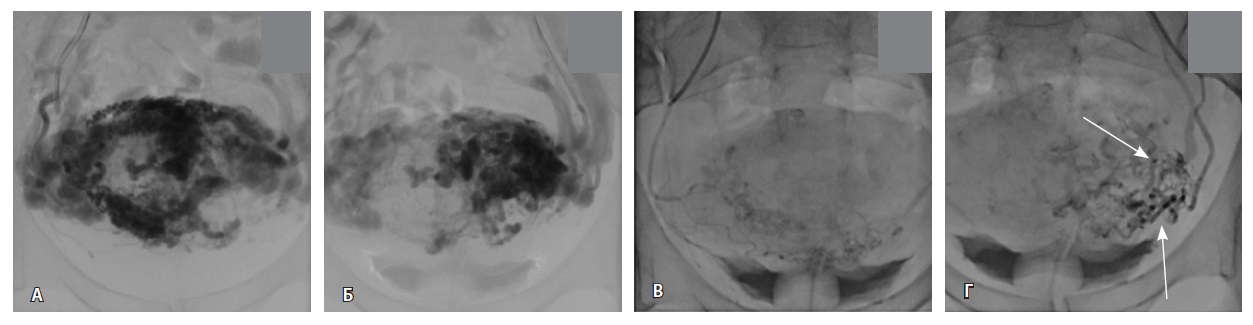

Исходя из клинической и визуальной картины, пациентке выполнено оперативное лечение. Первым этапом проведена эмболизация маточных артерий. Под местной анестезией раствором ропивакаина пунктирована правая лучевая артерия. Установлен интродьюсер 5F. Катетером НН последовательно катетеризированы левая и правая внутренние подвздошные артерии, выполнена ангиография. На ангиограммах: артериовенозная мальформация в проекции матки; афферентные артерии – маточные и цервиковагинальные – с обеих сторон, две ветви 1 мм в диаметре от левой внутренней подвздошной артерии; эфферентные сосуды – вены параметрия, внутренние подвздошные вены и яичниковые вены с обеих сторон (рис. 4).

Рис. 4. Данные рентгеноконтрастной ангиографии. А, Б – ангиограммы бассейнов правой и левой маточных артерий. Зоны патологической васкуляризации в проекции тела матки: массивная сеть измененных артерий и вен, ранний артериовенозный сброс в вены параметрия, внутренние подвздошные вены и яичниковые вены с обеих сторон. В, Г – ангиограммы бассейнов правой и левой цервиковагинальных артерий. Контрастирование зоны патологической васкуляризации в проекции шейки и нижнего отдела тела матки, ранний артериовенозный сброс в вены параметрия преимущественно слева и в левую внутреннюю подвздошную вену (стрелки)

Выполнена эмболизация маточных и цервиковагинальных артерий с обеих сторон материалом PVA (1000 мкм) и эмболами из гемостатической губки. На контрольных ангиограммах патологическое сосудистое сплетение не контрастируется, артериовенозный сброс устранен (рис. 5). Катетеры и интродьюсер удалены, выполнен компрессионный гемостаз, наложена асептическая давящая повязка. Контрастный препарат йодиксанол (320 мг йода/мл) – 300 мл. Эффективная доза – 1,8 мЗв.

Рис. 5. Контрольные снимки после эмболизации маточных и цервиковагинальных артерий. Ангиограммы бассейнов правой и левой внутренних подвздошных артерий. Правая маточная и цервиковагинальная артерии, а также патологическое сосудистое сплетение в их бассейне не контрастируются, ранний артериовенозный сброс устранен. Незначительное контрастирование сегмента патологической сети по единичной мелкой ветви внутренней подвздошной артерии справа, по двум мелким ветвям внутренней подвздошной артерии слева (указано стрелками)